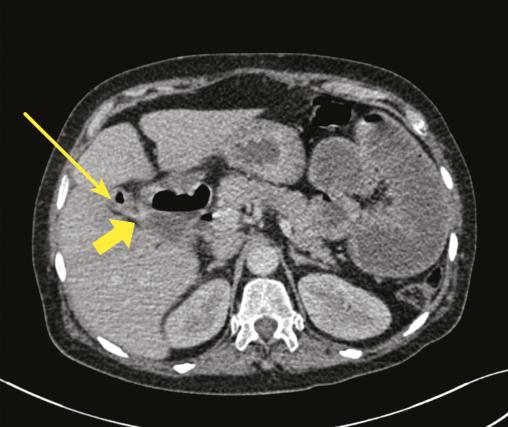

- une vésicule biliaire collabée, avec des bulles d’air (fig. 2) ;

- des bulles d’air au niveau des voies biliaires intra- et extra-hépatique (fig. 3) ;

- un trajet fistuleux entre la vésicule biliaire et le deuxième segment duodénal (fig. 2).